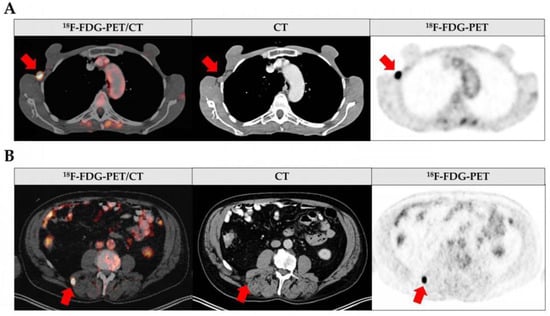

Overall, 63.8% of all whole-body 18F-FDG-PET/CT scans showed no sign of metastatic disease (Figure 2A). The most frequent site for metastasis was the lymph nodes, followed by soft tissue metastasis, lung metastasis, and liver metastasis in just one case (Figure 2A, Supplementary Table S1). The exemplary 18F-FDG-PET/CT scans showing lymph node and soft tissue metastasis are depicted in Figure 3. Based on the 18F-FDG-PET/CT results, the subsequent diagnostic or therapeutic procedure was altered in 40 out of the 94 cases (42.6%; Figure 2B). In most cases, the type of subsequent surgical intervention changed (65%; Figure 2C). Namely, locoregional lymph node dissection, the targeted resection of suspect lymph nodes, and the resection or biopsy of soft tissue or other distant metastases were performed. Four patients instead received neoadjuvant immunotherapy (10%), while two patients refused surgery after imaging (5%; Figure 2C). In 20% of the cases with an altered procedure, this was due to the first diagnosis of a secondary malignancy either directly suspected upon interpretation of the 18F-FDG-PET/CT scans or histologically verified after initially being considered melanoma metastasis (Figure 2C). The histology revealed two cases of non-Hodgkin lymphoma, two cases of prostate carcinoma, one case of colon carcinoma as part of Lynch syndrome, one case of mamma carcinoma, one case of carcinoid tumor, and one case of giant cell tumor.

Figure 3. Images from 18F-FDG-PET/CT at melanoma diagnosis. Fused 18F-FDG-PET/CT (left), CT (middle) and 18F-FDG-PET (right) scans. Metastases are indicated by red arrows. (A) shows an axillary lymphatic metastasis in a 55-year-old patient and (B) depicts a metastasis in the autochthonous back muscles in a 66-year-old patient.

By combining metabolic and morphological information, 18F-FDG-PET/CT is a powerful tool for detecting metastasis in oncology and melanoma staging (Figure 3) [14]. The value of this imaging method is widely accepted for the detection of distant metastases [20]. Lymph node metastases, however, are assumed to be reliably detectable only at a size of 6 mm and larger [22]. Since lymph node metastases are the most frequent and earliest form of metastasis in malignant melanoma, their detection is crucial in melanoma staging. This raises the question as to whether whole-body imaging is nevertheless suitable for initial melanoma staging as it is recommended for patients from AJCC stage IIC (>4 mm tumor thickness and ulceration) onwards [9].